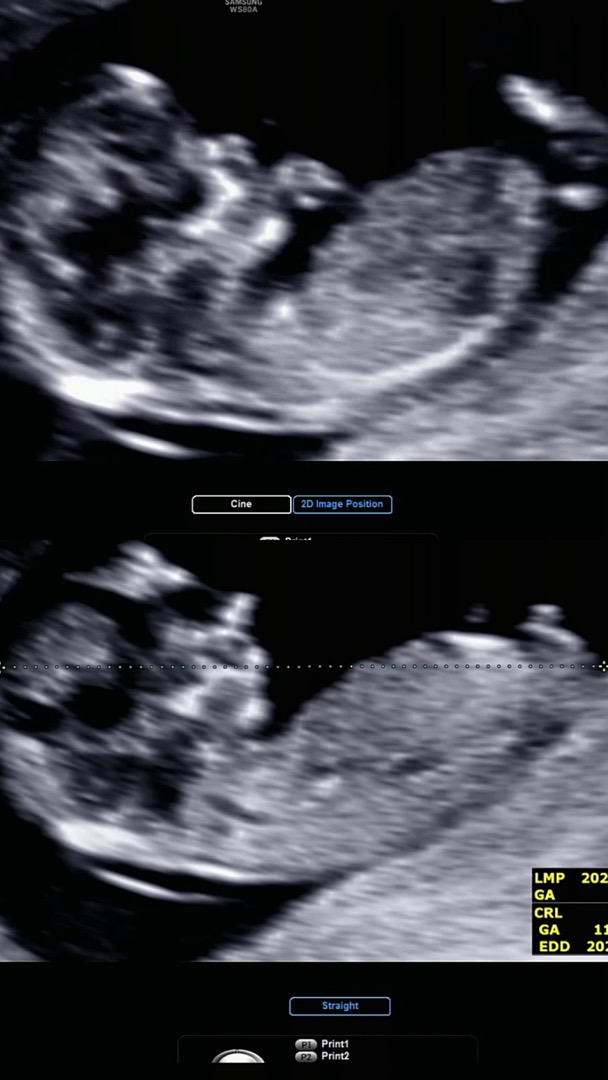

12주차 들어서서 1차 기형아검사랑 정밀초음파 보고왔어요! 성별 힌트는 얻지못했네요 혹시 각도법 고수님들 계신가요 ㅠㅡㅠ저는 예시 사진 암만봐도 모르겠네요 아기가 각도가 너무 다양해요…같은 아기인데 힝